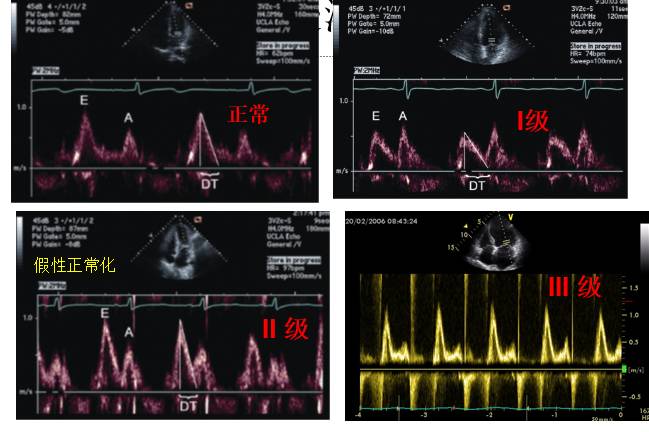

二尖瓣血流充盈模式

◆由E/A比值及DT决定的

◆正常、松弛功能障碍(I级)、LV假性正常化充盈(II级)及LV限制性充盈(III级)。

◆不典型的模式,如三相二尖瓣血流速度模式。